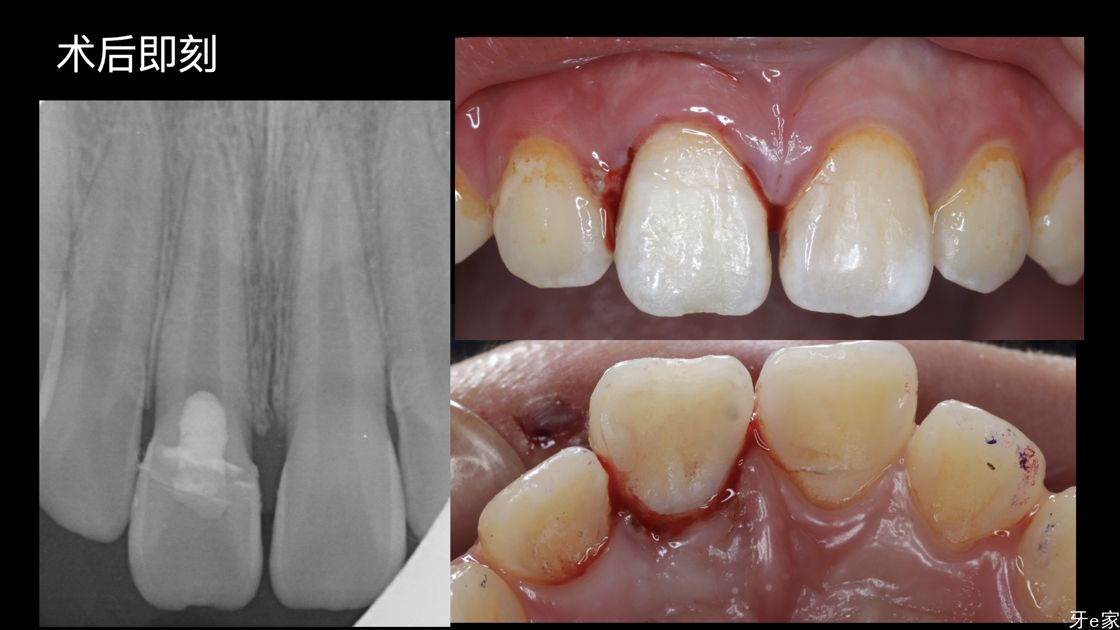

术中治疗